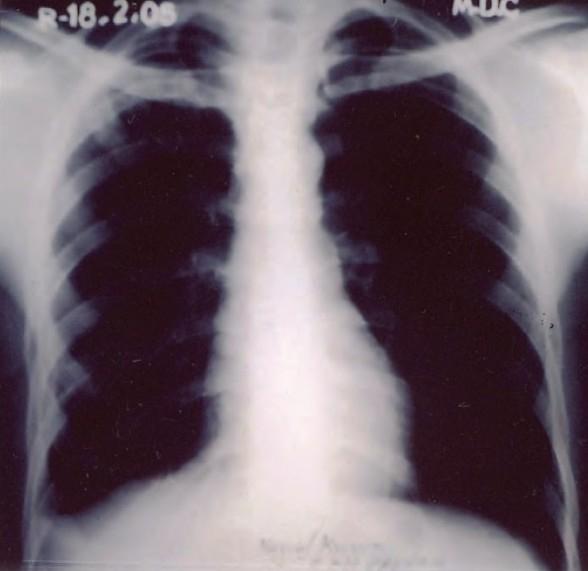

A 24-year old male developed left sided pleural effusion 10 days after the start of anti tubercular chemotherapy for right-sided pleural effusion and parenchymal lesion. This effusion seemed to be a paradoxical response as it resolved on follow up.

一名24岁男性在开始针对右侧胸腔积液和实质病变进行抗结核化疗10天后出现左侧胸腔积液。这种积液似乎是一种反常反应,因为在随访中它自行消退了。